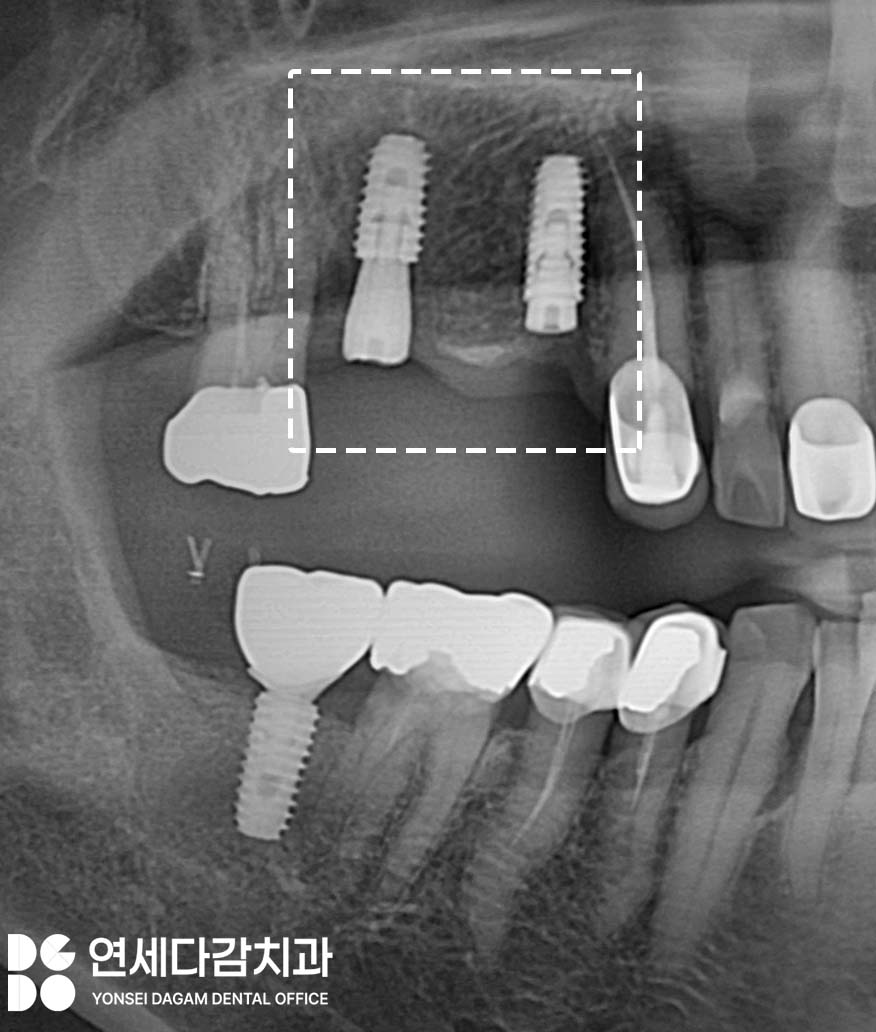

발치 즉시 임플란트 과정을 통해

자연치가 있던 자리에 임플란트를 식립하면

빠른 회복을 도모할 수 있습니다.

이 방법은 뼈 손실을 최소화하고

치료 기간을 단축할 수 있는 장점이 있습니다.

치료 과정에서 옆에 크라운이

씌워져 있던 부위 인접면에도

충치가 발견되어,

치료 후 다시 크라운을 새로 제작하여

가능한 한 자연치 보존을 하게 됩니다.